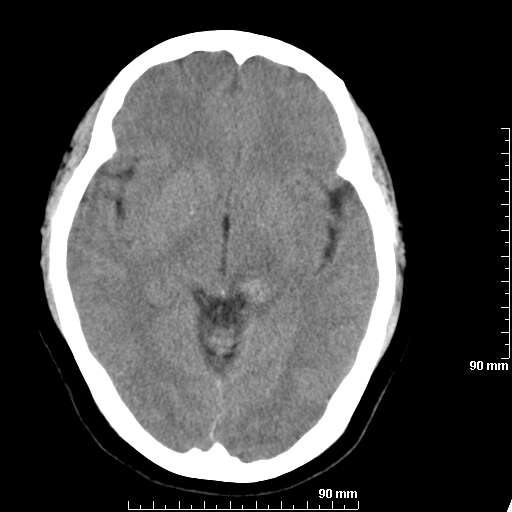

[维修案例解析] 大家猜猜看,这个伪影是怎样产生的.

我院西门子单排CT由于一零件受损而产生的伪影.

哈哈,都不是。是虑线器fiter裂损。大家没想到吧。

哦,跟脑出血有点像哦

形状不规则,边缘模糊。比较特殊的一种伪影哈!

这种伪影很常见!伪影应该是在视野的中心的。

西门子的虑线器fiter裂损这才是很难见的问题,GE的最常见

虑线器老化,中间崩裂一块掉了